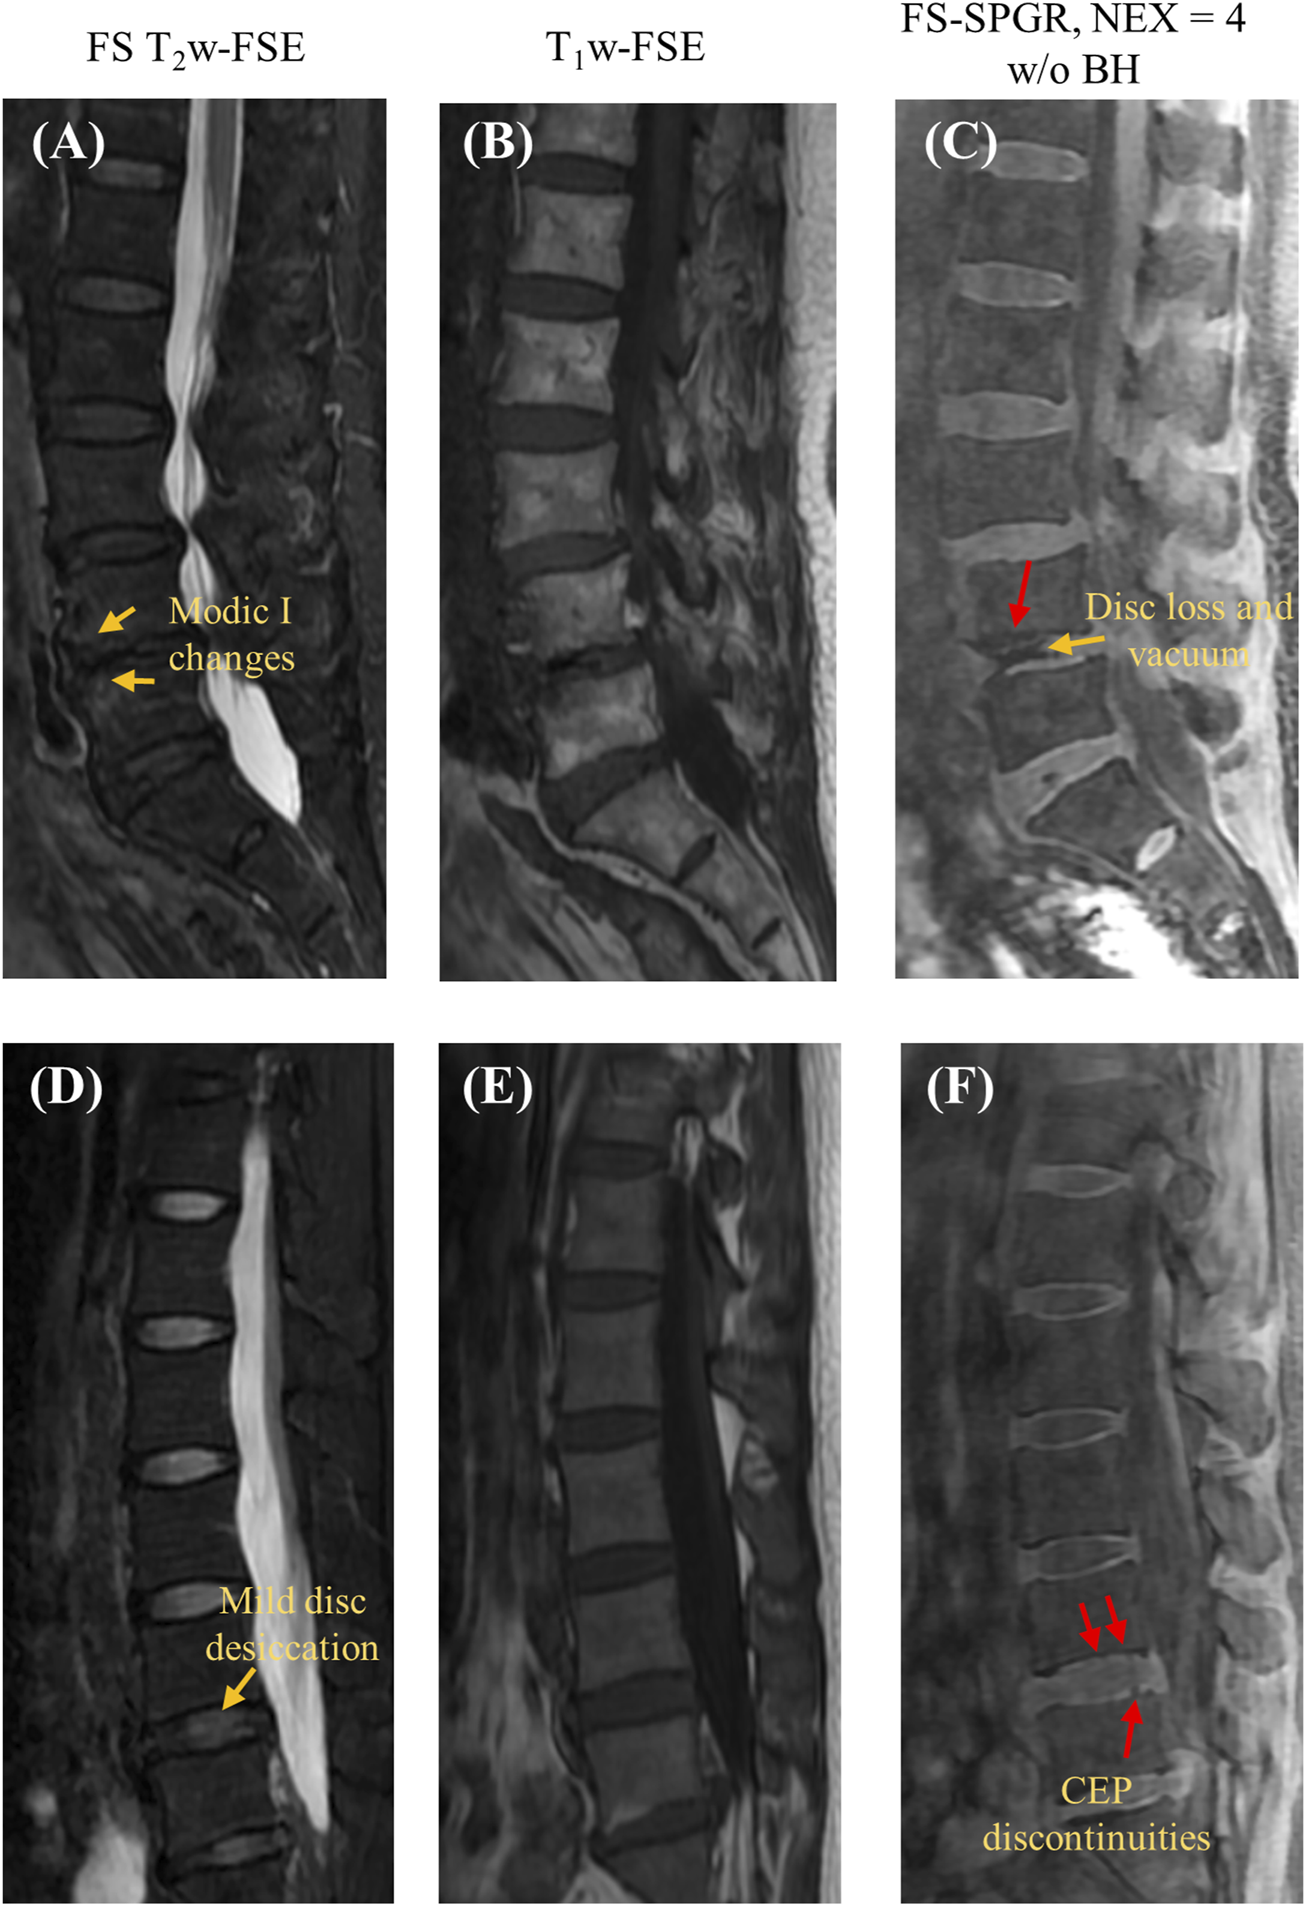

Figure 4 shows the FS-SPGR images alongside clinical images obtained from two female patients (70 and 46 years old, respectively) with lower back pain. For Figures 4A–C, the degenerative disc disease is evident at L4-5, characterized by disc loss, vacuum phenomenon, and anterior fibrovascular marrow changes (Modic I) and osteophytes. The CEP regions at this level are both grossly abnormal, though with different appearances. The inferior L4 CEP displays a hypointense appearance, consistent with a change in composition, while the superior L5 CEP is mildly hyperintense and significantly thickened. Both changes are consistent with the CEP dysfunction. For Figures 4D–F, there is mild disc desiccation at the L4-5 with associated subtle changes of the CEPs (arrows point to foci of hyperintensity consistent with compositional change). Additionally, mild disc desiccation is observed at the L5-S1 level, featuring a small area of anterior fatty marrow replacement (Modic II change). The anterior half of the L5-S1 CEPs appear hypointense, consistent with compositional alterations.

FIGURE 4

Clinical FS T2w-FSE (A,D) and T1w-FSE (B,E) images as well as 3D FS-SPGR (free breathing, NEX = 4) (C,F) images acquired from two patients with lower back pain (first row: 70-year-old female; second row: 46-year-old female). The CEP discontinuities are indicated by red arrows in panels (C,F) while the other pathologies, namely, Modic I changes [panel (A)], mild disc desiccation [panel (C)] and disc loss and vacuum [panel (C)] are marked by yellow arrows.